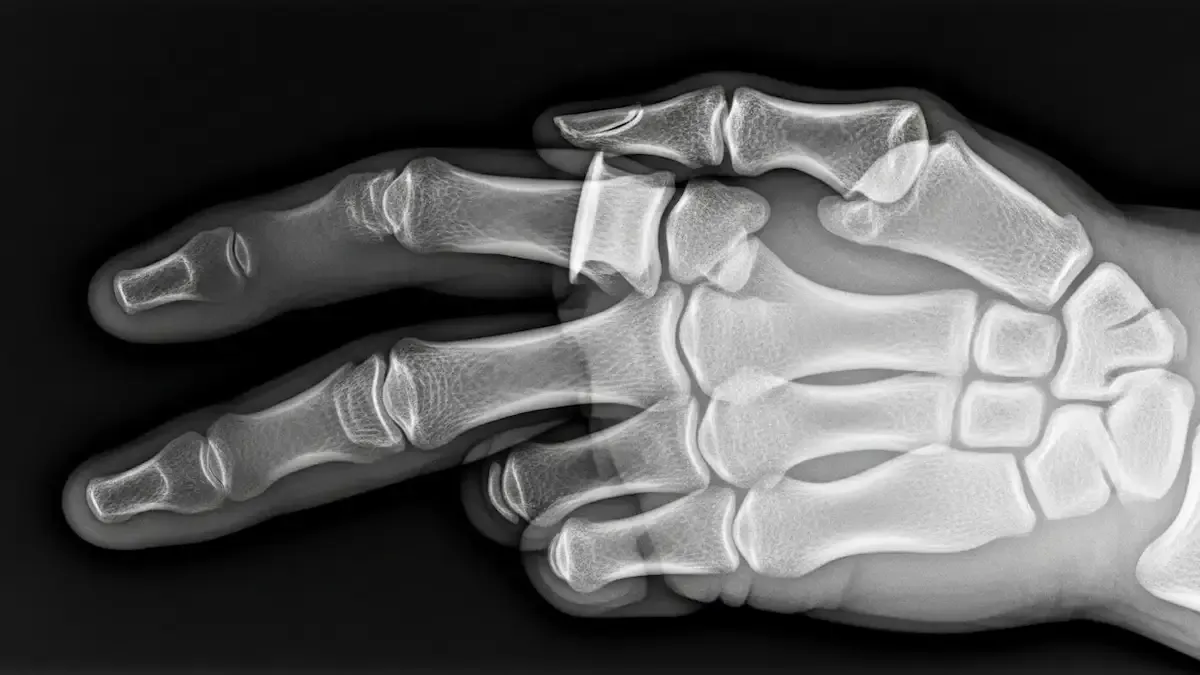

Como é feito o diagnóstico

O diagnóstico começa com o exame clínico, avaliando o alinhamento, a mobilidade e a estabilidade do dedo.

Radiografias em diferentes ângulos são solicitadas para confirmar a luxação e descartar fraturas associadas.